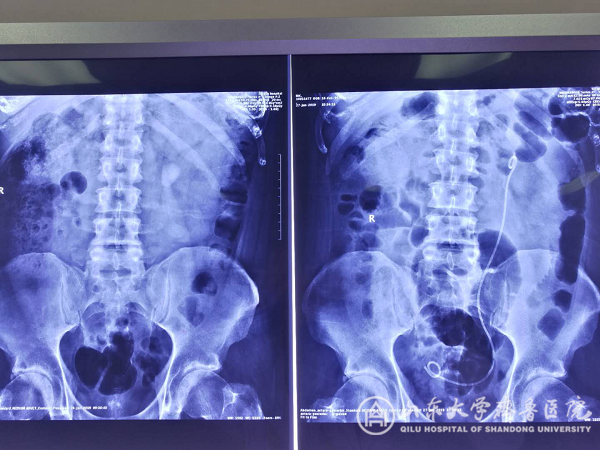

【本站讯】近日,在中国工作的英国教师RIK因患肾结石慕名来我院就诊,入院后泌尿外科二病区主任史本康主持全科讨论,由张东青教授团队为其行微通道无管化经皮肾镜碎石术,术中顺利将其3cm结石完全粉碎并排出,术后第1天即下床,第2天出院,住院时间仅5天。患者在围手术期未感觉到疼痛,对医护人员表示了由衷的感谢。

微通道无管化经皮肾镜碎石术相比于传统术式,其特点是患者痛苦小恢复快,手术创面仅为5mm刀口,但要求术者精准穿刺,拥有娴熟的通道扩张技巧及碎石清石技术。该技术已在我院开展近1年,受到广大患者一致认可。